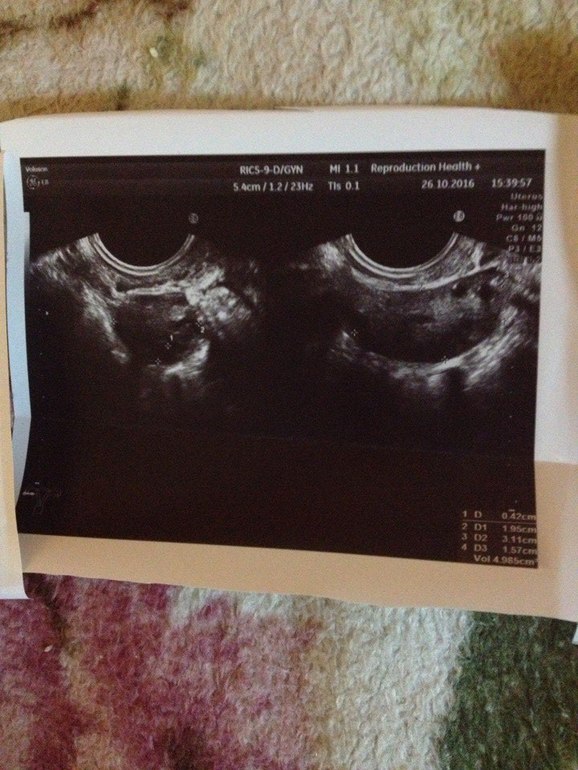

Девочки,может,кто понимает в узи?

Узистка сказала ничего нет в матке..Да и толком вообще ничего не говорила..я спросила: а внематочной есть риск? в ответ: Я не знаю. Через месяц приходите-посмотрим...Я в тихом ужасе..Не знаю что делать..22 ДЗ..

Лада, к сожалению на представленом узи-фото действительно не видно плодного яйца. Но вы не паникуйте раньше времени, может еще появится.